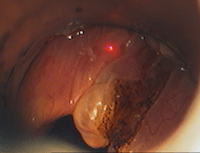

Patient avec dysphonie (voix cassée): sous anesthésie générale par jet ventilation (tuyau sous les cordes vocales): découverte de lésion de la corde vocale gauche. Après biopsie de cette lésion, l'examen anatomo-pathologique révélera une tuberculose laryngée isolée et exclura l'hypothèse diagnostique de cancer (carcinome épidermoïde).